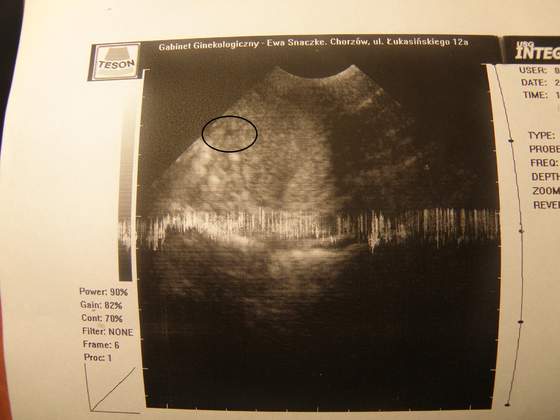

Ehh tak oglądam wasze maleństwa i też nie mogę się doczekać własnej fotki

byłam 2 tygodnie temu, alew niestety nie dostałam zdjęcia, chociaż maleństwo było już widać (może dlatego nie dostałam, że byłam na NFZ), w środę idę prywatnie i na pewno dostanę :-)